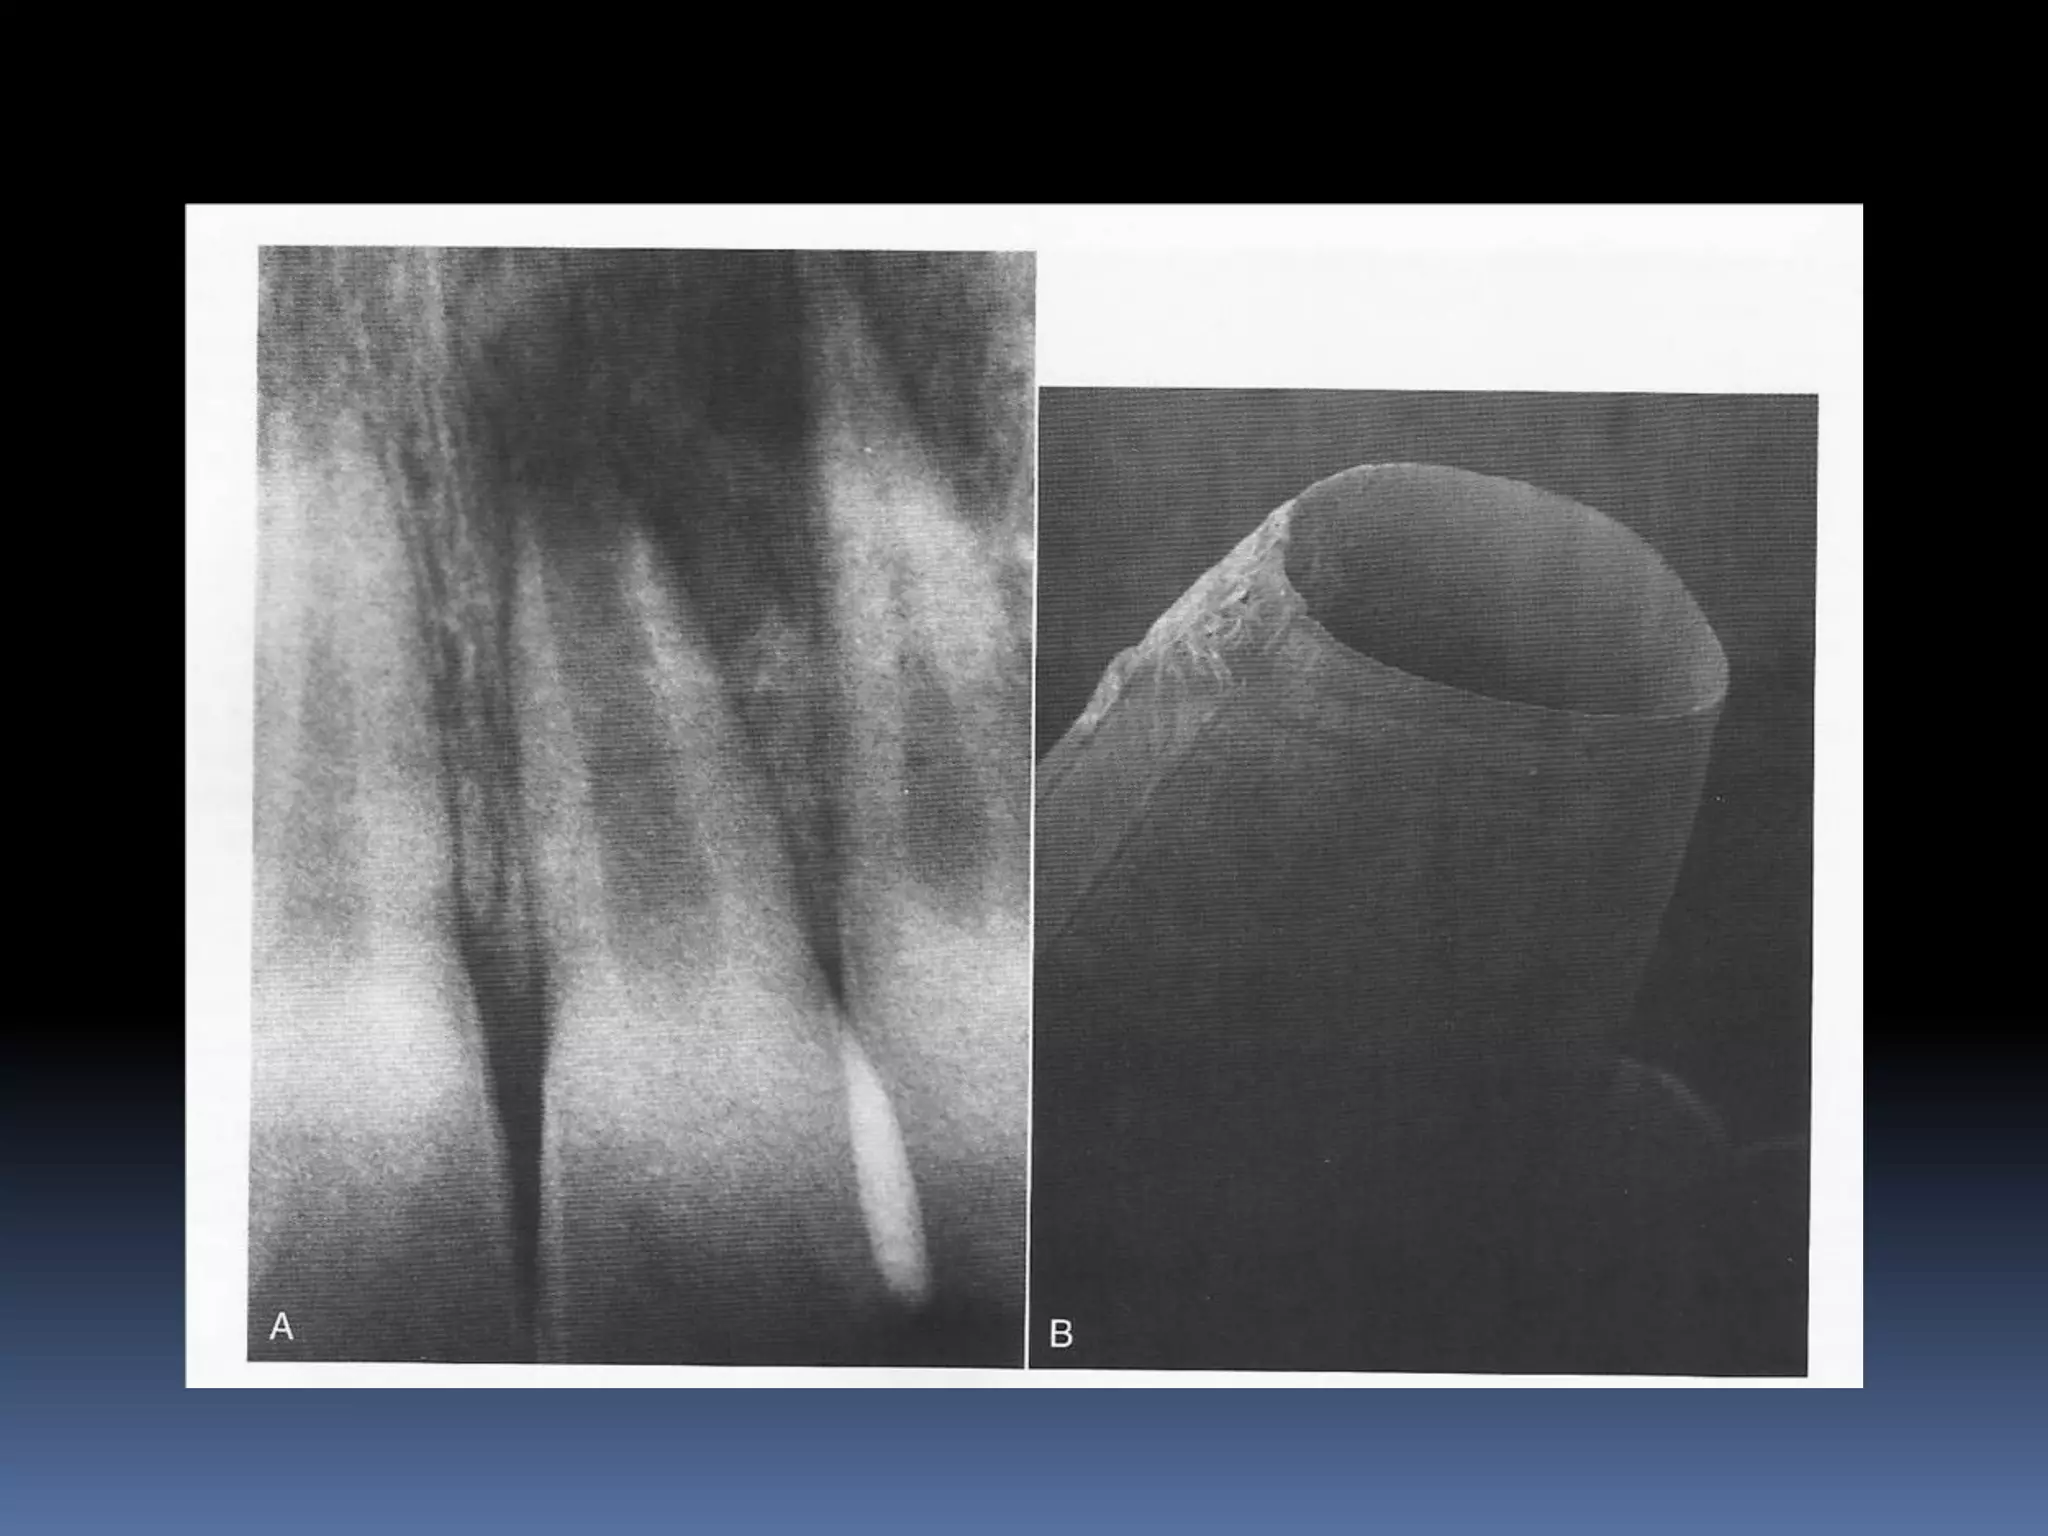

OPEN APEX  Anopen apex is the developing root of an immature tooth until apical closure occurs .  Apical closure occurs 2-3 yrs after tooth eruption  Any injury to the pulp at this stage will stop the closure of the apex  Such a tooth will have short , thin walls at the apical portion of the root

• 32.

 Open apexcan also be caused by extensive resorption of a previously mature apex after orthodontic treatment or severe periapical inflammation

Diagnosis and assessment: History  Subjective symptoms  Diagnostic tests  Radio graphs A radiolucent area usually surrounds the apex of an immature root with a healthy pulp

• 34.

• 41.

APEXIFICATION Induction of acalcific barrier or creation of an artificial barrier across an open apex Technique: Local anesthesia and Rubber Dam isolation Access cavity preparation and extirpation of the pulp Working length is established slightly short of the apex [to prevent injury to apical tissues] Instrumentation and copius irrigation Drying the canal and introducing MTA into the canal

• 42.

 Packing MTAusing endodontic pluggers or special system like MAP SYSTEM [Micro Apical placement]  MTA acts as an artificial barrier against which Gutta percha can be condensed.  Calcium hydroxide produces a biologic barrier but takes longer time.